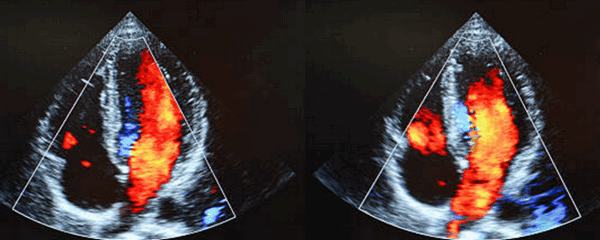

Эхокардиография при аномальном дренаже легочных вен

Аномальные соединения легочных вен на эхокардиографии

На эхокардиографии аномальный дренаж легочных вен (AДЛВ) устанавливается, когда некоторые или сразу все легочные вены не соединяются непосредственно с левым предсердием. При этом, если только некоторые вены аномально соединяются, то состояние на УЗИ сердца описывают как частичный АДЛВ, а если все вены аномально впадают не в левое предсердие, то устанавливается диагноз полный (тотальный) АДЛВ. Существует множество возможных аномальных соединений из легких вен с сердечными камерами или экстракардиальными сосудами.

Особенности эхокардиографии при аномальном дренаже легочных вен

Адекватную визуализацию легочных венозных соединений необходимо получить из нескольких плоскостей визуализации. У младенцев и детей, надгрудинная коронарная плоскость сканирования с задней ангуляцией может продемонстрировать позицию «краб», из которой можно посмотреть, что происходит с соединениями из четырех легочных вен у корпуса левого предсердия (или венозном впадение при ПАДЛВ). Однако, потенциал для множественных соединений сосуществует в таком пациенте, что делает усердный поиск легочных вен довольно трудным, поэтому врач на эхокардиографии использует все имеющиеся плоскости, обязательные в этих случаях.

В нормальном сердце, апикальная четырехкамерная позиция на УЗИ сердца показывает связи правой и левой нижних легочных вен на задней и нижней области левого предсердия (ЛП). Субкостальная четырехкамерная и сагиттальное сканирование позволяет визуализировать соединения правой верхней легочной вены в ЛП. Кроме того, из этих позиций, может быть визуализирован дефект венозного синуса. Левую верхнюю легочную вену часто можно увидеть в парастернальной короткой оси или из надгрудинного сканирования, описанного выше. У пациентов с увеличением правого сердца, сканирование с правой паразитарной области часто обеспечивают четкое изображение предсердий перегородки и легочных вен.

Если вход всех легочных вен в ЛП не визуализируется уверенно, необходимо провести исчерпывающий поиск для оценки возможных аномальных связей. Это часто одна из самых сложных задач при врожденных пороках сердца в эхокардиографии. Чреспищеводная эхокардиография (ЧПЭХОКГ) полезна в определении дренажа правых легочных вен, даже когда они аномальны. ЧПЭХОКГ должна быть использована в случаях необъяснимого расширения правого предсердия для того, чтобы исключить ЧАДЛВ.